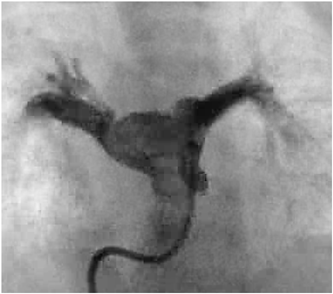

A 25-day-old girl with a complicating RS virus infection was transferred to our hospital because of respiratory distress. Enhanced computed tomography (CT) showed that the right PA originated from the posterolateral wall of the ascending aorta (Fig. 1). Echocardiography revealed that the right ventricle (RV) was remarkably dilated, with a flattened interventricular septum (Fig. 2A) and moderate tricuspid regurgitation (TR) with a pressure gradient of 68 mmHg, suggesting excessive PH. Echocardiography also showed a 5.7-mm-wide atrial septal defect (ASD) with bidirectional shunting. Due to the RS virus infection and requirement for ventilator support, right PAB was planned for initial palliation to avoid cardiopulmonary bypass.

Fig. 1 Preoperative enhanced computed tomography with three-dimensional reconstruction in Case 1

The right branch of the pulmonary artery originated from the posterolateral wall of the ascending aorta. RPA: right pulmonary artery, Asc Ao: ascending aorta

Fig. 2 (A) Preoperative and (B) postoperative echocardiography in Case 1

(A) The RV was remarkably dilated, with a flattened interventricular septum. (B) The deformity of the interventricular septum was improved. RV: right ventricle, LV: left ventricle

At 36 days of age, right PAB was performed through a median sternotomy using a 2-mm-wide expanded polytetrafluoroethylene (ePTFE) tape. The right PA was gradually tightened to a circumference of 14.5 mm with the band. At that time, the peak blood flow velocity across the right PA was 4.2 m/s. The systemic arterial pressure was finally elevated to 20 mmHg under 100% oxygen and nitric oxide (NO) inhalation. After this surgery, we were able to start aggressive PH therapy using tadalafil and macitentan to improve RV function. This patient was extubated on postoperative day (POD) 24, and NO inhalation was discontinued on POD 32. Echocardiography showed that the deformity of the intraventricular septum had improved, and the TR was trivial with a pressure gradient of 42 mmHg (Fig. 2B). Postoperative cardiac catheterization after right PAB demonstrated that the left pulmonary vascular resistance (PVR) was still high at 10.7 units·m2. However, her left lung reacted well to oxygen supplementation, and the patient was therefore considered to be a good candidate for total correction. After the development of bacterial pneumonia, her cardiac function and PH deteriorated, and mechanical ventilation was required on POD 45. After improvement of the PH and heart failure by antibiotic therapy, total correction was achieved 72 days after the initial palliation.